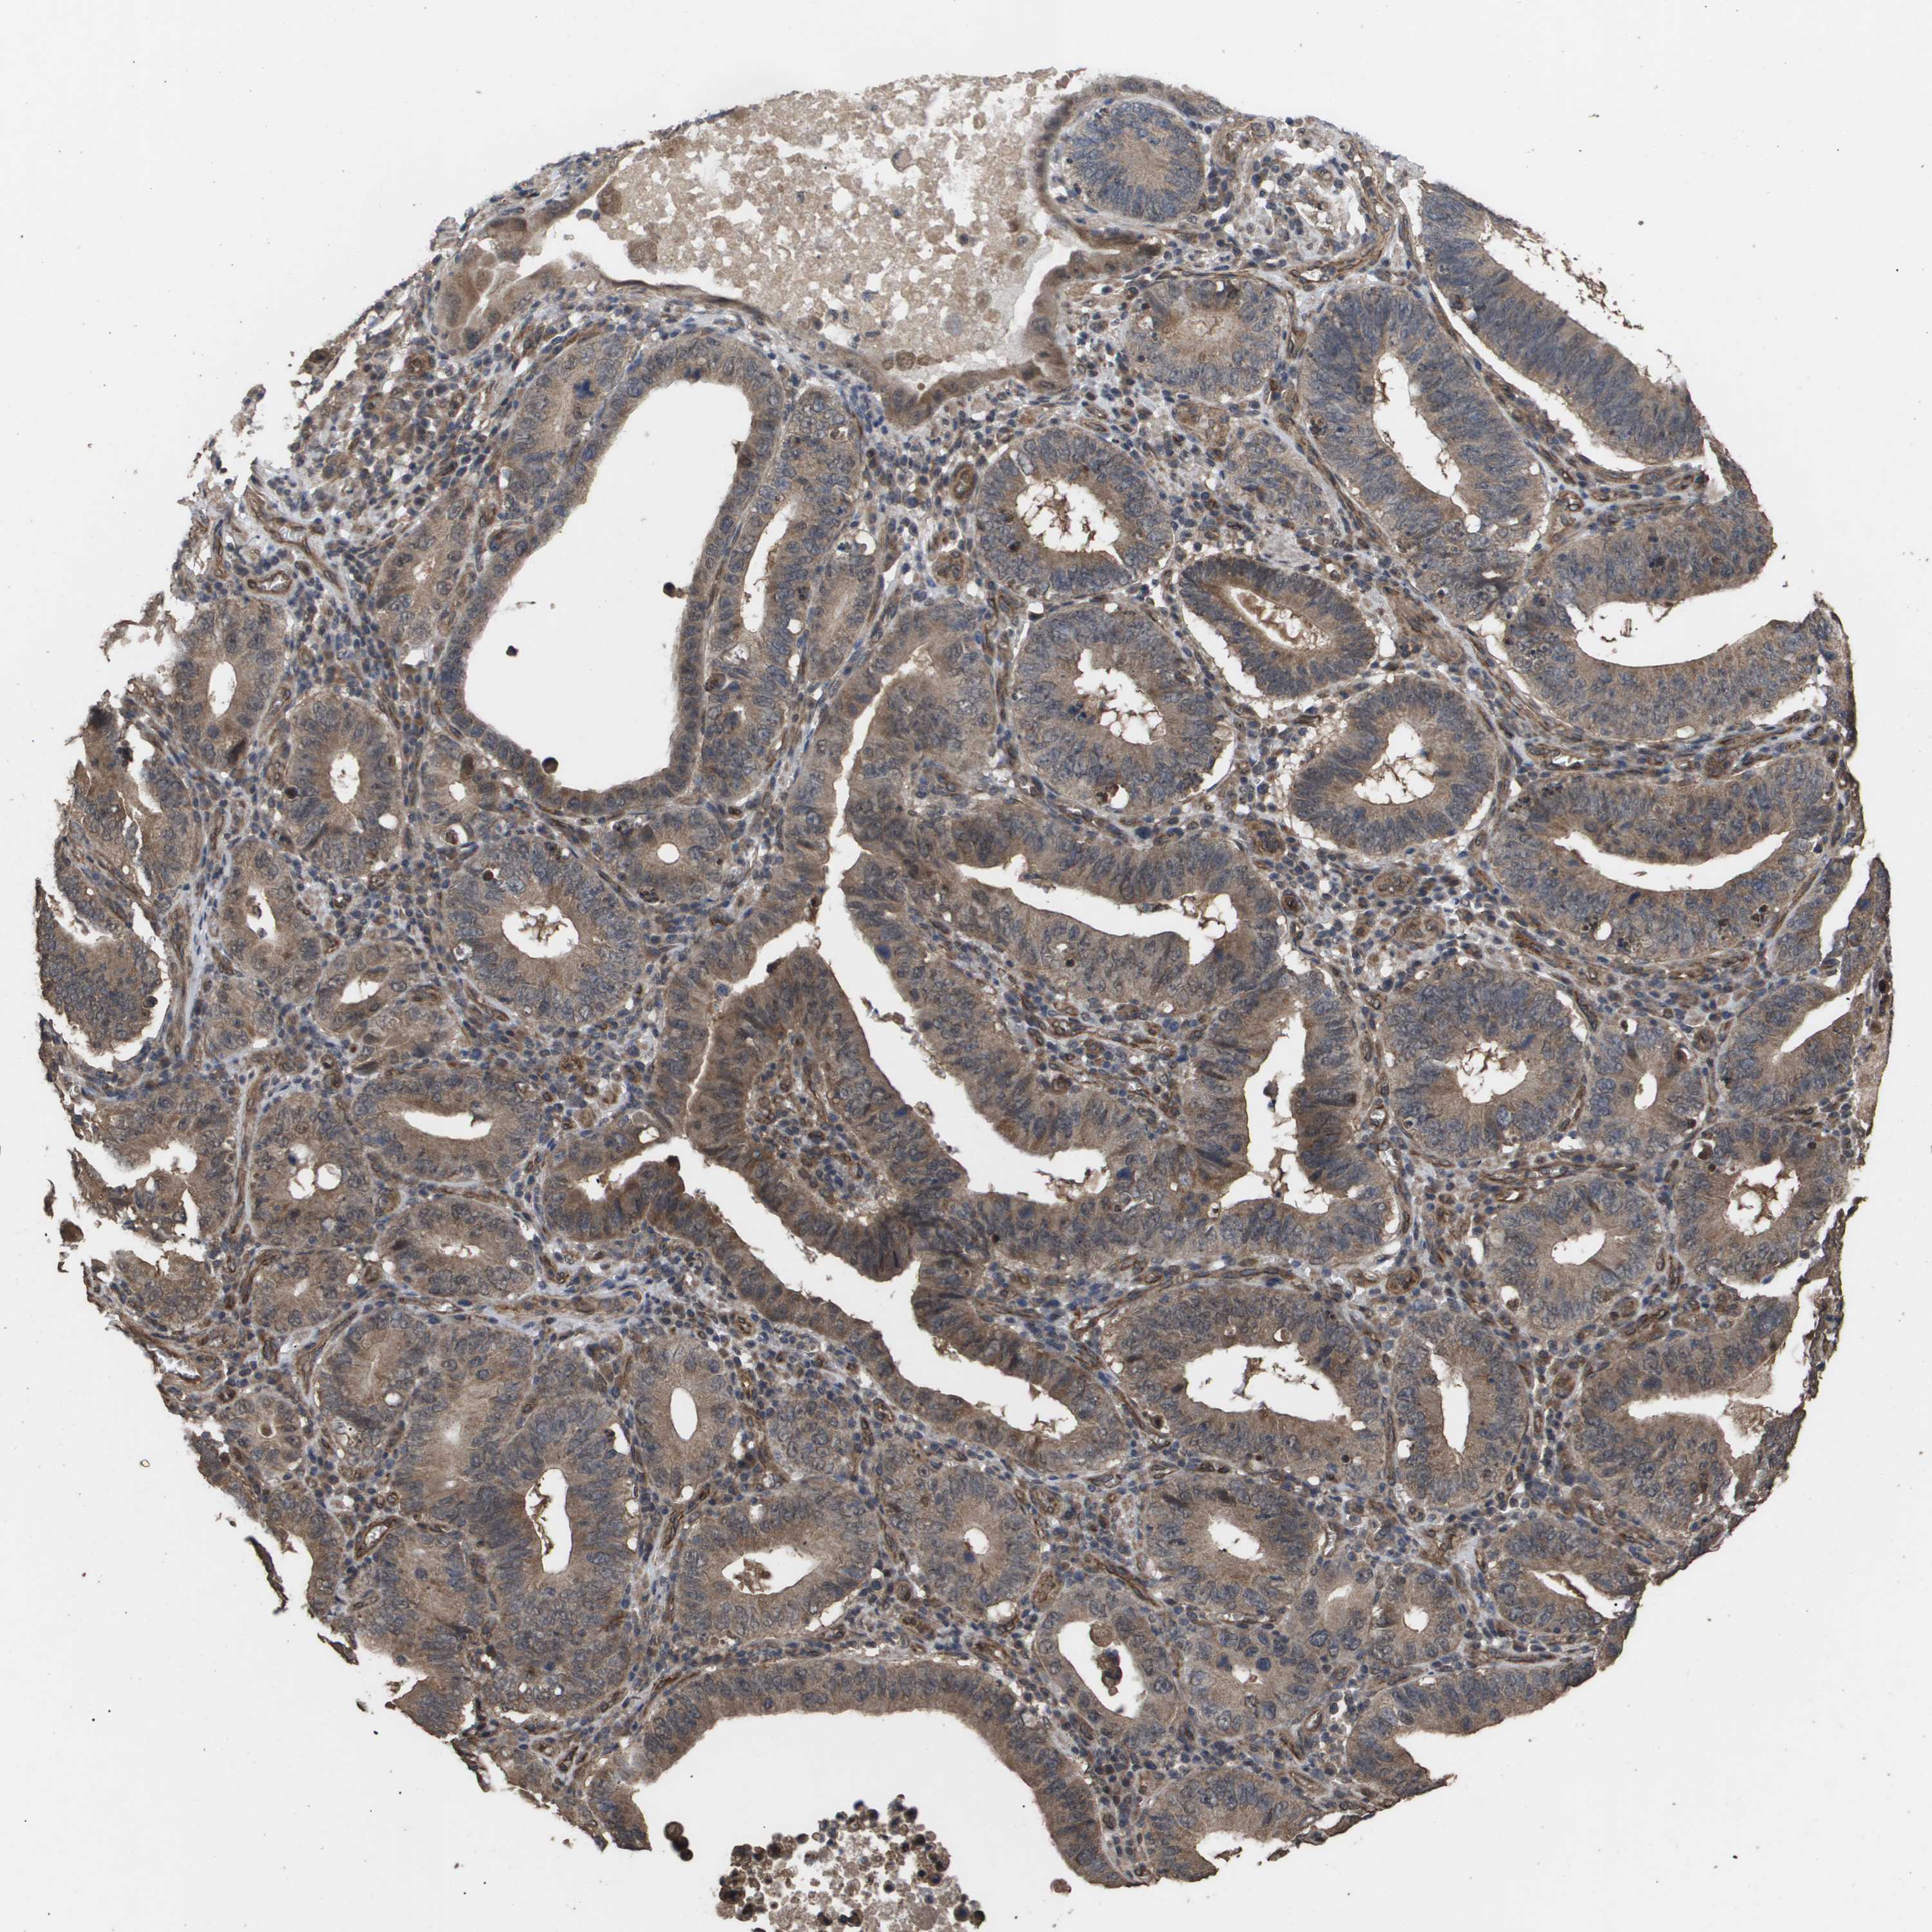

STOMACH CANCER - Protein expressioni

A mouse-over function shows sample information and annotation data. Click on an image to view it in a full screen mode. Samples can be filtered based on level of antibody staining by selecting one or several of the following categories: high, medium, low and not detected. The assay and annotation is described here.

Note that samples used for immunohistochemistry by the Human Protein Atlas do not correspond to samples in the TCGA dataset.

Antibody stainingi

Antibody staining in the annotated cell types in the current human tissue is reported as not detected, low, medium, or high, based on conventional immunohistochemistry profiling in selected tissues. This score is based on the combination of the staining intensity and fraction of stained cells.

Each image is clickable and will lead to virtual microscopy that enables deeper exploration of all samples and also displays staining intensity scores, fraction scores and subcellular localization as well as patient and tissue information for each sample.

Antibody HPA002185

Antibody CAB017787

Staining

High

Medium

Low

Not detected

Intensity

Strong

Moderate

Weak

Negative

Quantity

>75%

75%-25%

<25%

None

Location

Nuclear

Cytoplasmic/membranous

Cytoplasmic/membranous,nuclear

Adenocarcinoma, NOS

Adenocarcinoma, High grade